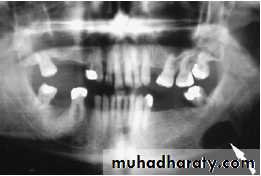

Stone formation (sialothiasis): most common cause of obstruction within the submandibular gland is within the gland and duct system.

80%of all salivary stones occur in the submandibular glands because highly viscous secretions .

80% submandibular stones are radio-opaque

Obstruction and trauma to submandibular gland